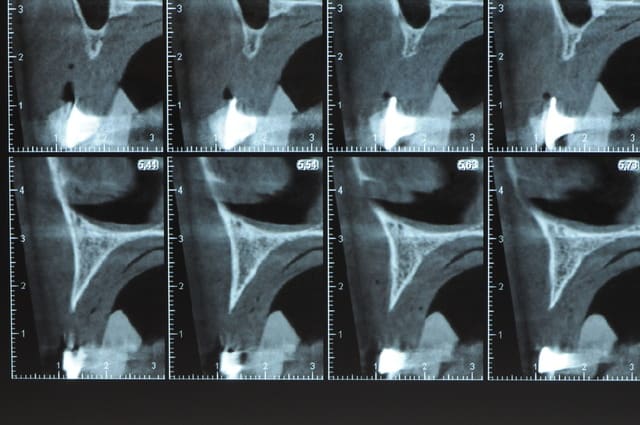

j'ai besoin de 4 implants au maxillaire pour faire tenir son complet.

dans la zone postérieur, pas de problème, mais devant, c'est une autre histoire.

la corticale a l'air tiptop, par contre en cas d'expansion il faut eventuellemnt augmenter le nombre d'implant à 6 pour compenser eventuellement le manque d'epaisseur 'avis personnel)

Je suis sceptique sur la gestion de ce cas par bone splitting puisqu'il met parait très difficile d'obtenir un volume osseux peri-implantaire crestal suffisant et satisfaisant.

+1 Olive, ce serait à mon avis plus prédictible avec des greffes. Je doute qu'on puisse obtenir suffisamment d'os en vestibulaire et en palatin des implants en splittant une crête aussi fine.

Ce n'est pas vraiment un consensus mais plutot du bon sens. Si tu as une crête en profil de lame de couteau cela signifie que tu as une fusion des corticales vestibulaire et palatine et donc absence de spongieux, ce qui comme tu le sais n'est pas indiqué en implanto (cj os de marbre par exemple)

Il me semble que Palti ou encore Szmukler-Moncler recommandent un minimum de 2-3mm. Si c'est plus fin, greffe d'apposition et GBR.

Dans ton cas il te faudrait abaisser la crête de 3 bons mm pour arriver à cette épaisseur.

Une petite étude de ton cas D57

Sous réserves bien sur de voir l’animal en vrai

Les zones exploitables radiologiquement parlant:

Coupes implant

2,3 40100

4,96 35130 avec sinus lift mais difficile

5,25 35150

6,02 35130

6,78 35115 après réduction de hauteur de crête

7,26 35115 après réduction de hauteur de crête

8,51 35150

10,43 40115 ou 50115

11,10 40115

Ce qui nous fait 9 implants possible évidement avec un comblement de sinus on augmenterait encore les zones implantable mais ce n’est pas le but recherché, avec 8 (4+4) il doit être possible de faire une belle barre support de complet